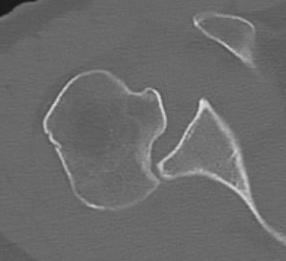

CT scan

Confirms dislocation

Reverse Hill Sachs

Humeral head defect

- caused by impaction of anterior humeral head on posterior glenoid

- intra-articular

- measured as a percentage of the articular surface